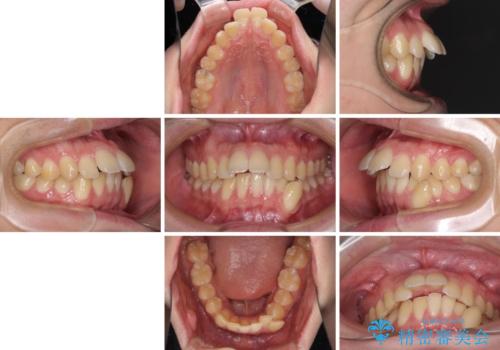

出っ歯と八重歯 目立たない裏側装置でスッキリとした口元に

- 20代男性

- 矯正装置

- ハーフリンガル

- 治療期間

- 4年5ヶ月

- 上顎の前突感による口の閉じにくさと八重歯を気にして来院された患者様です。

目立たない装置を希望されたので、上顎が裏側装置のハーフリンガルを選択し、上下左右の小臼歯(計4歯)を抜歯して矯正治療を行うこととしました。

下顎骨が左側に大きく変位しているため、上下の正中位置は極力一致するところをゴールとしました。

上下顎で左右差の大きい抜歯矯正を裏側装置で行ったため、非常に時間がかかりましたが、正中位置も良い位置に改善され、気になっていた突出感も解消されました。